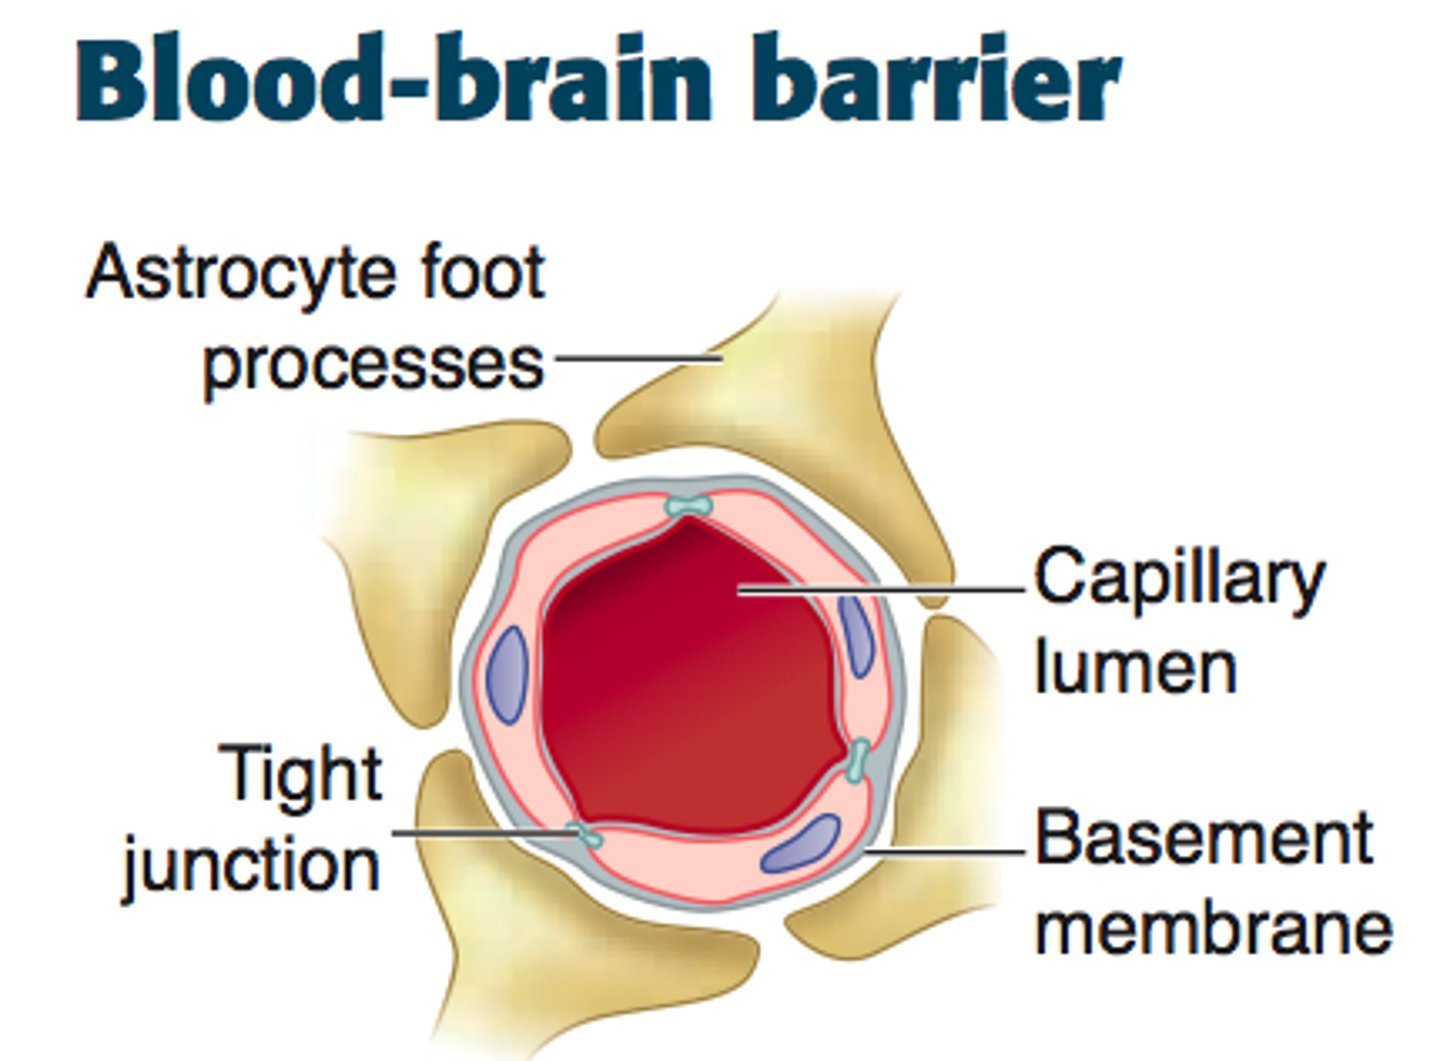

Blood Brain Barrier

Tight junctions between endothelial blood vessel cells cause substances to pass through cells to become Cerebrospinal fluid (CSF),

Not completely uniform in all areas

Blood brain barrier and tight junction/ substances becoming CSF

1) Large substances/molecules cannot utilize the route between cells and are barred from CSF.

2) Lipid-soluble substances, such as nicotine, ethanol, and heroin, can diffuse through the endothelial cell membranes and enter the brain.

3) Water-soluble molecules such as amino acids and glucose move across by mediated transport

Blood brain barrier not completely uniform in all areas:

1) Very permeable in vomiting venter in brain stem

- allows monitoring of blood for poisonous substances

2) Very permeable in hypothalamus

- allows sampling of chemical composition of blood to regulate water balance, body temp, etc.